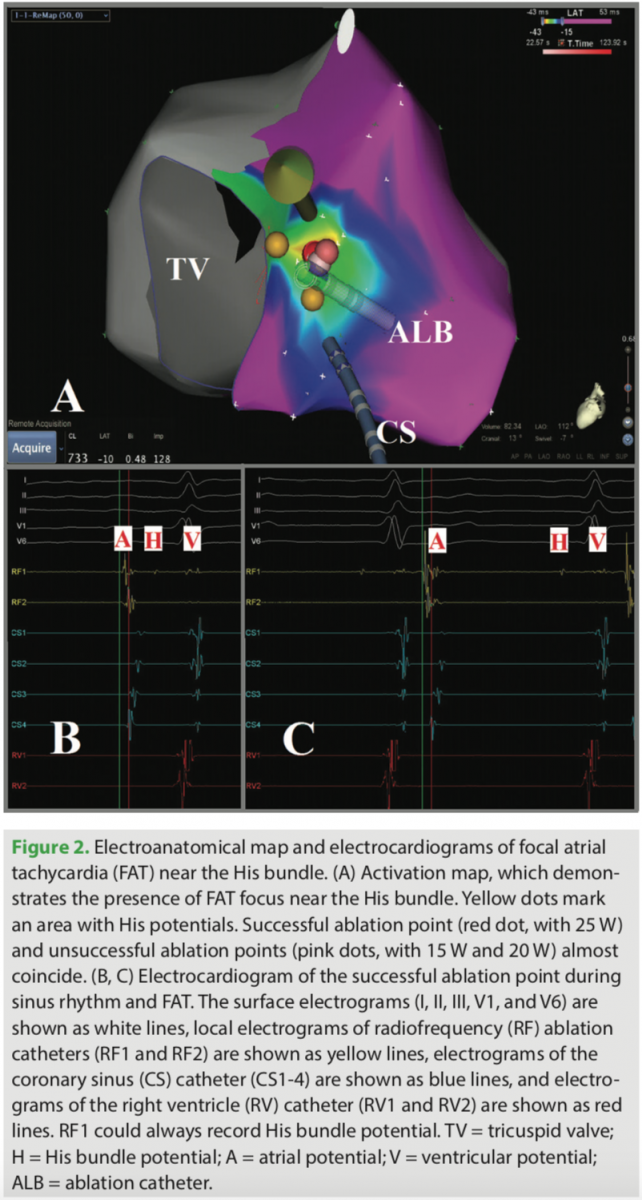

In addition, we analyzed acute success rate, long-term follow-up success rate, and re-occurrence rates from other aspects, including age and origin of the foci. These parameters were similar not only in the two age groups, but also between the patients with left- and right-sided foci. These results reflected that RMN offers distinct advantages both for the procedure itself, and for the outcomes when performing complex ablation procedures. Consequently, we believe that RMN ablation may provide precise and stable catheter positioning (Figure 2), a reduction in the incidence of major complications, and a reduction of exposure to fluoroscopy.19,20